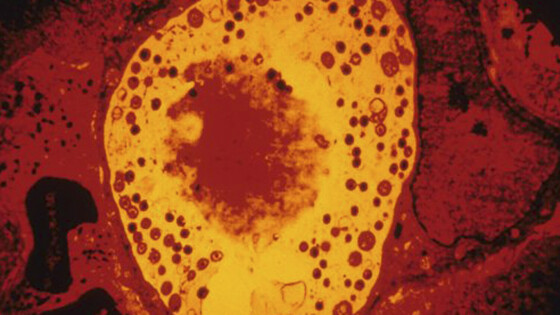

Анализ показал, что у пациентов с болезнью Альцгеймера в тканях сетчатки и головного мозга обнаруживались значительно более высокие концентрации хламидий. Это род грамотрицательных бактерий, виды которых относятся к облигатным внутриклеточным паразитам. Хламидии вызывают заболевания у человека, животных и птиц.

Чтобы разобраться в механизме, исследователи провели эксперименты на мышах. Они показали, что присутствие хламидий активирует хроническое воспаление, гибель нервных клеток и выработку бета-амилоида — токсичного для нейронов белка, накопление которого считается одной из центральных особенностей болезни Альцгеймера. В совокупности эти процессы ускоряли нейродегенерацию.